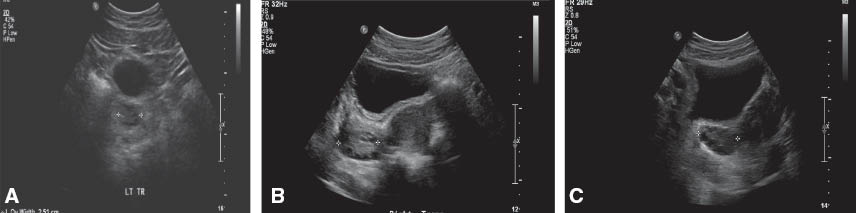

Morphological characteristics of ovaries include number and location of the follicles distributed within the ovary, stromal echogenicity, and vascularization (17). Silfen et al. reported that 100% obese PCOS and 75% non-obese PCOS patients had multiple peripherally oriented ovarian follicles, compared with 31% of controls (11). Shah et al. and Pawelczak et al. reported that more than 80% of obese adolescent PCOS patients had >10 follicles located peripherally (10, 14). Figure 1 shows the peripherally located follicles in obese and non-obese PCOS adolescents, compared with a normal ovary. Figure 2 shows both transabdominal and transvaginal ultrasound of a polycystic ovary in an overweight PCOS adolescent.

Transabdominal transverse ultrasound images (A) normal ovary. (B) Right ovary in a non-obese adolescent with PCOS (ovarian volume 13 mL). Several small follicles are peripherally located, without evidence of a dominant follicle. (C) Right ovary in an obese PCOS adolescent (ovarian volume 17 mL). Several small follicles are also peripherally located. Body habitus limits the quality of the image.

The pathophysiology leading to this ultrasound finding is thought to be explained by phenomena put forth by Panchal et al. Androgen leads to proliferation of stromal and theca cells, leading to increased stroma. As the disease progresses and the stroma expands, the follicles in the central part of the ovary move out to the periphery, leading to a peripheral polycystic ovary. A peripheral cystic pattern is suggestive of a long-standing, more severe disease (17). Thus, the number and distribution of ovarian follicles, even in the absence of an enlarged ovarian volume, can be suggestive of PCOS in adolescents. The radiological findings are most useful when combined with the clinical and biochemical findings consistent with PCOS (10).